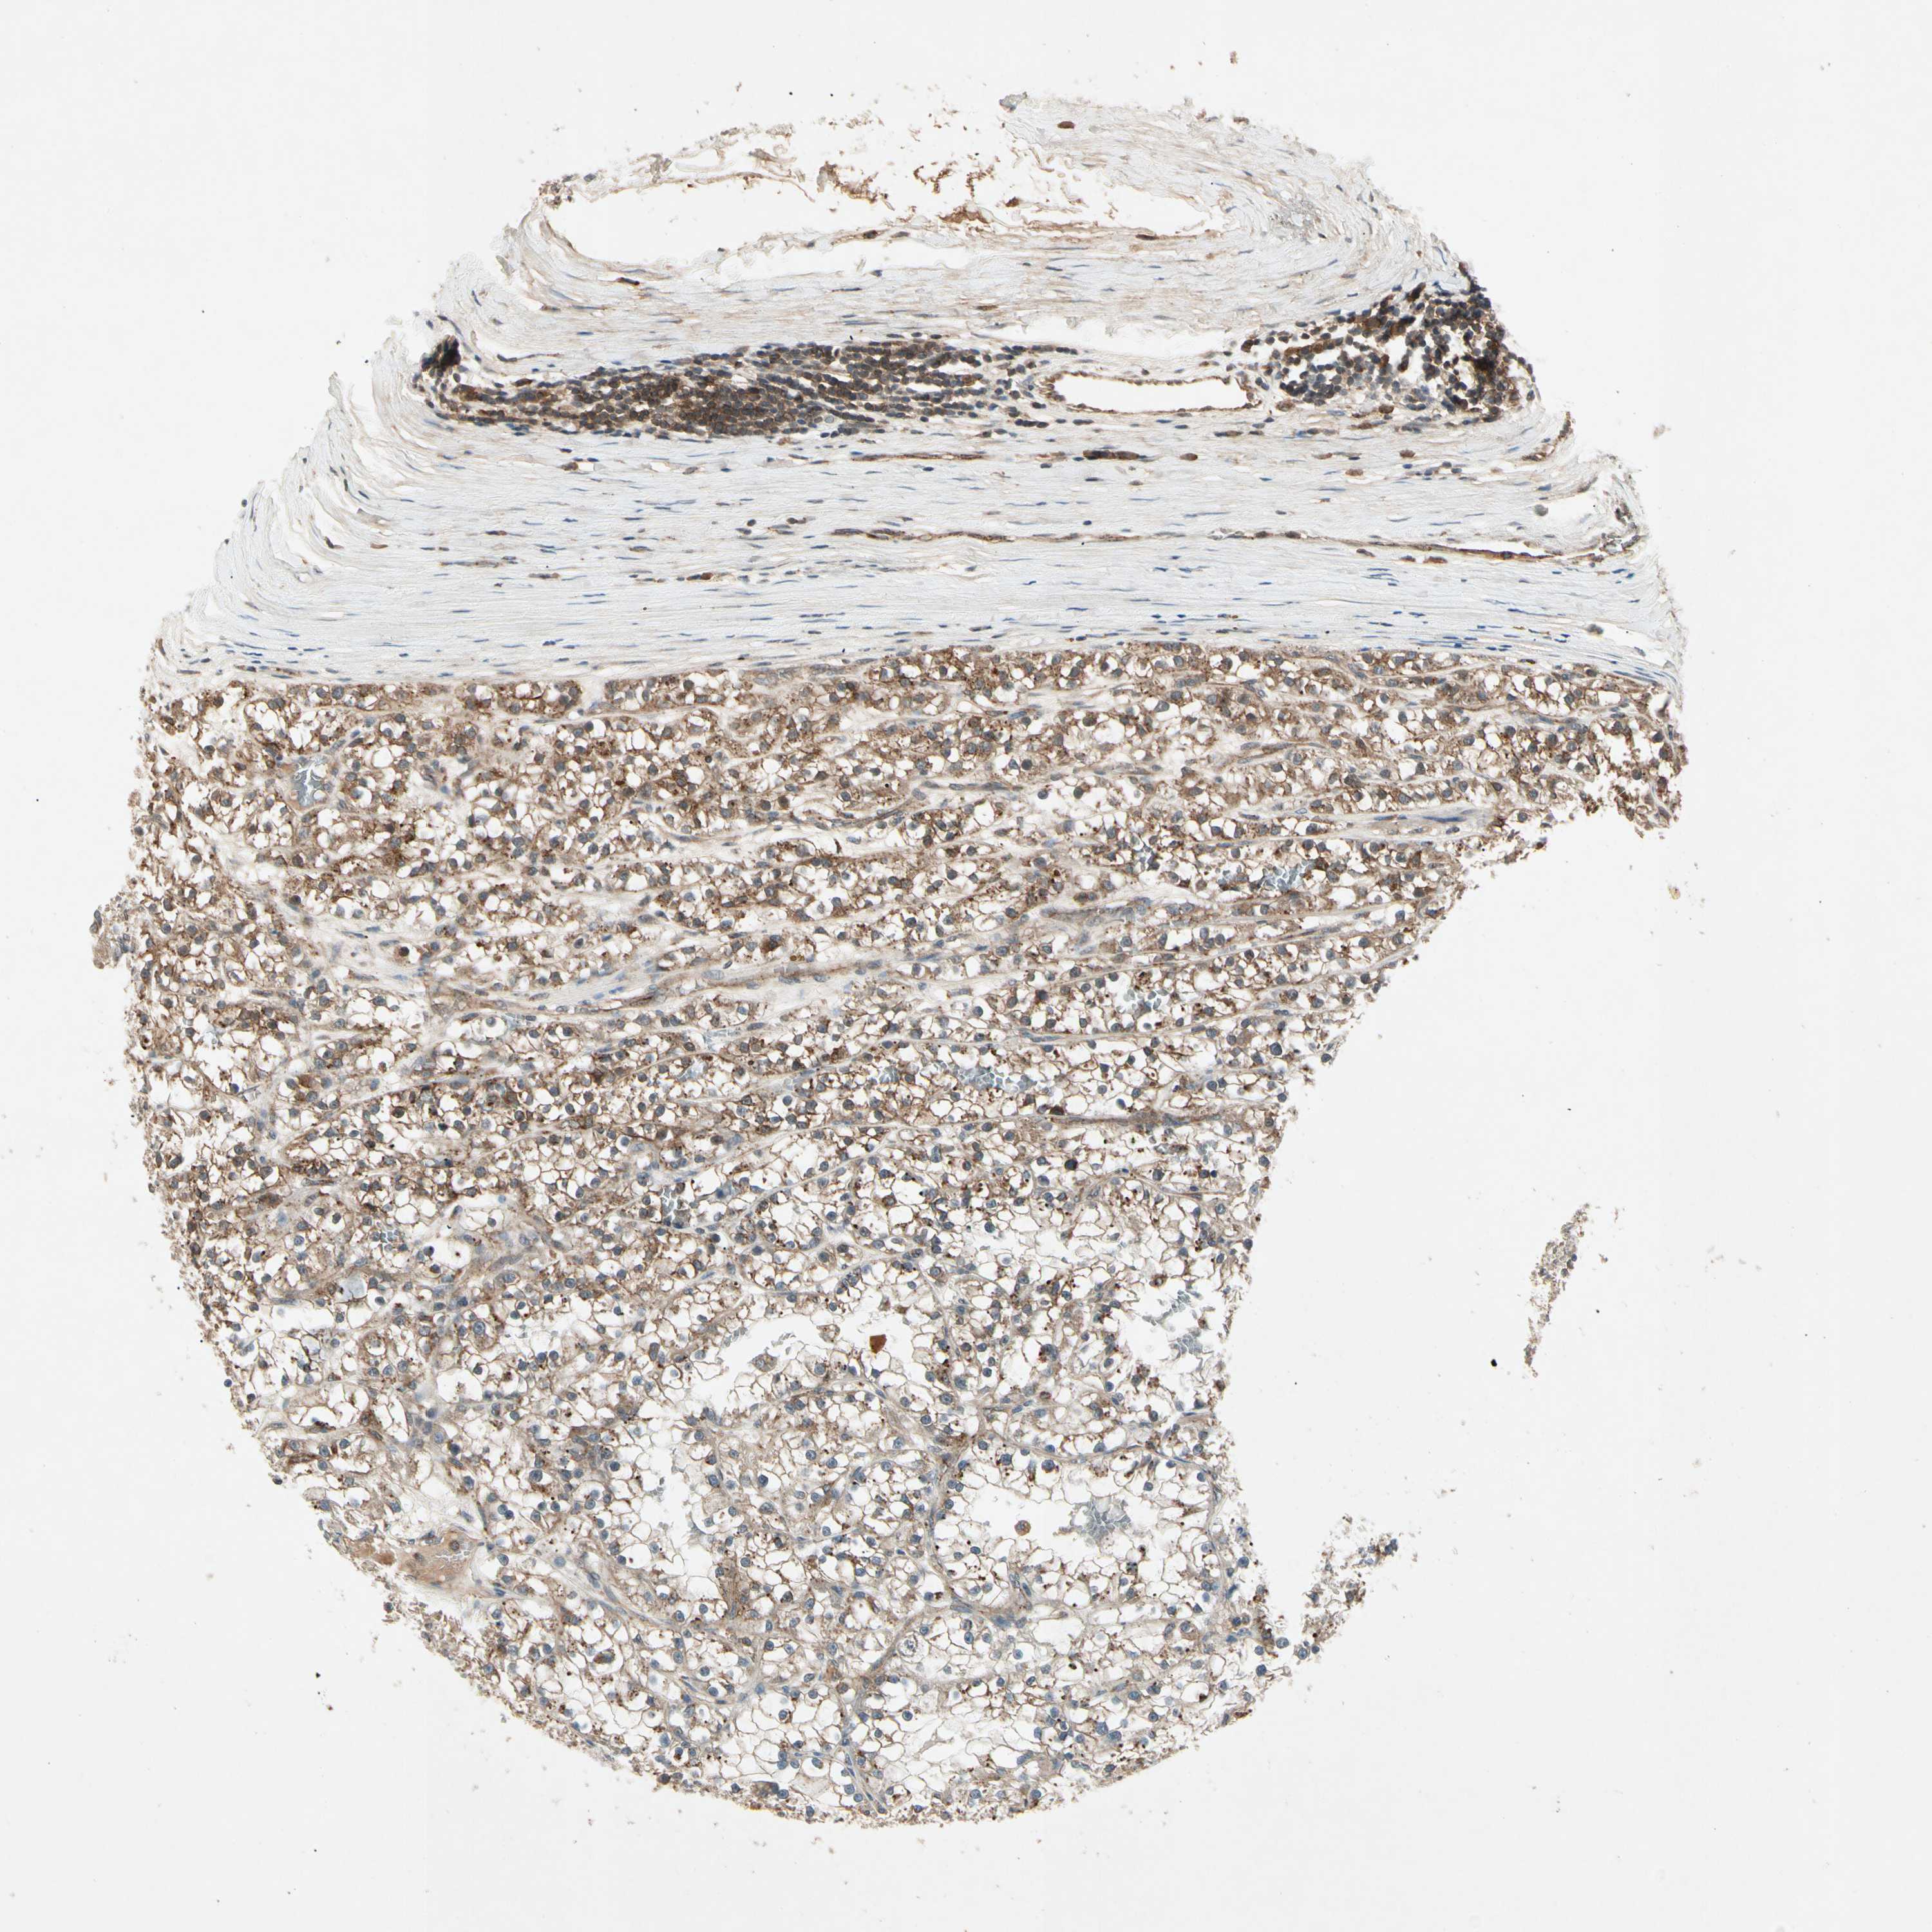

KIDNEY RENAL CLEAR CELL CARCINOMA (TCGA) - Interactive survival scatter ploti

The Survival Scatter plot shows the clinical status (i.e. dead or alive) for all individuals in the patient cohort, based on the same data that underlies the corresponding Kaplan-Meier plots. Patients that are alive at last time for follow-up are shown in blue and patients who have died during the study are shown in red.

The x-axis shows the expression levels (FPKM) of the investigated gene in the tumor tissue at the time of diagnosis. The y-axis shows the follow-up time after diagnosis (years). Both axes are complimented with kernel density curves demonstrating the data density over the axes. The top density plot shows the expression levels (FPKM) distribution among dead (red) and alive patients (blue). The right density plot shows the data density of the survived years of dead patients with high and low expression levels respectively, stratified using the cutoff indicated by the vertical dashed line through the Survival Scatter plot. This cutoff is automatically defined based on the FPKM cutoff that minimizes the p-score. The cutoff can be changed by dragging the vertical line or by entering a cutoff value in the square labeled "Current cut-off".

Under the Survival Scatter plot the p-score landscape (black curve; left axis) is shown together with dead median separation (red curve; right axis). Dead median separation is the difference in median mRNA expression between patients who have died with high and low expression, respectively. It is calculated as follows: median FPKM expression of dead patients with high expression - median FPKM expression of dead patients with low expression. This is intended to aid the user in visually exploring custom cutoffs and the associated p-scores and dead median separation.

Individual patient data is displayed and can be filtered by clicking on one or more of the category buttons on the top of the page. Categories describing expression level and patient information include: high, low, alive, dead, female, male and tumor stages. The scale of the x-axis can be toggled between linear and log-scale by clicking on the "x log" button. Mouse-over function shows TCGA ID, patient information and mRNA expression (FPKM) for each patient.

& Survival analysisi

Kaplan-Meier plots summarize results from analysis of correlation between mRNA expression level and patient survival. Patients were divided based on level of expression into one of the two groups "low" (under cut off) or "high" (over cut off). X-axis shows time for survival (years) and y-axis shows the probability of survival, where 1.0 corresponds to 100 percent.

FLOT1 is potential prognostic, high expression is favorable in Kidney Renal Clear Cell Carcinoma (TCGA)

Best expression cut offi

Based on the FPKM value of each gene, patients were classified into two groups and association between prognosis (survival) and gene expression (FPKM) was examined. The best expression cut-off refers the FPKM value that yields maximal difference with regard to survival between the two groups at the lowest log-rank P-value. Best expression cut-off was selected based on survival analysis .

When clicking on this number, the vertical dashed line indicating cut-off, the interactive survival plot, and the Kaplan-Meier curve will be adjusted to show results based on the best expression cut-off.

: 45.45

TCGA RNA samplesi

RNA-seq data is reported as average FPKM (number Fragments Per Kilobase of exon per Million reads), generated by the The Cancer Genome Atlas (TCGA) .

Normal distribution across the dataset is visualized with box plots, shown as median and 25th and 75th percentiles. Points are displayed as outliers if they are above or below 1.5 times the interquartile range. FPKM values of the individual samples are presented next to the box plot.

Average pTPM 64.8

Number of samples 521